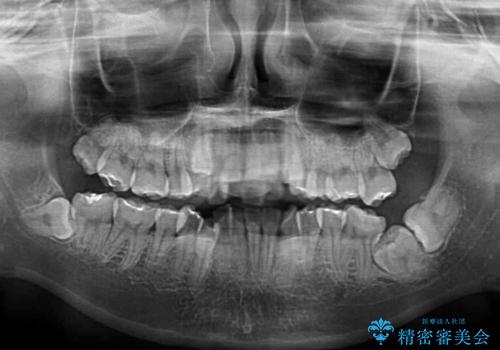

転位歯や埋伏歯などの難易度の高い抜歯矯正治療

- 八重歯や埋伏している奥歯など、多くの難しい問題を抱えている患者様です。

重度叢生のため、大臼歯をしっかりと咬合させるために、下顎は左右第二小臼歯を、上顎は前歯部の叢生を解消するために左右第一小臼歯を抜歯し、口元の突出感を改善するために、上顎大臼歯が前方に移動しないようにするために、補助装置による架強固定を行うこととしました。